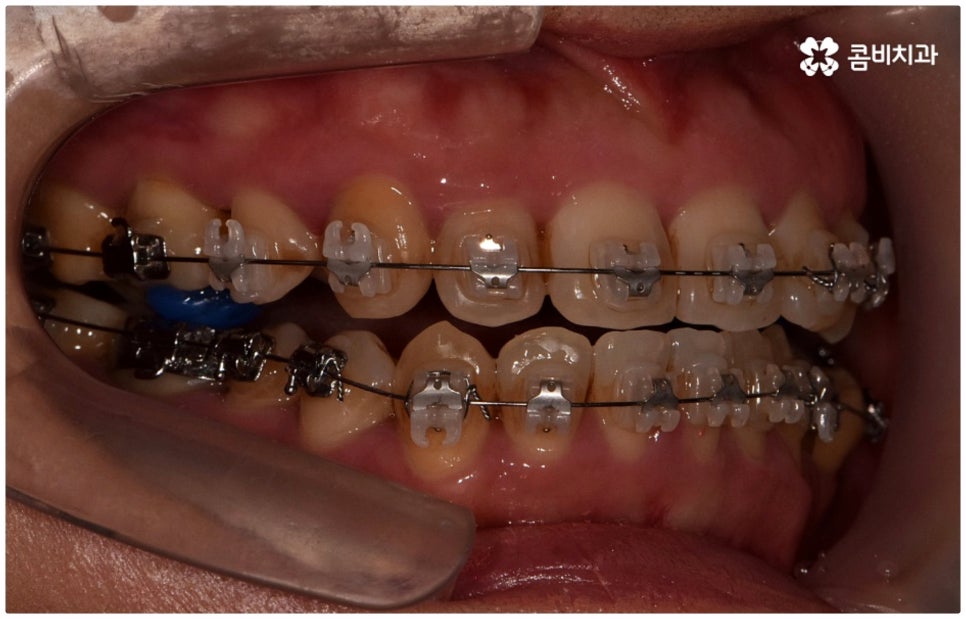

골격적인 원인으로 인한 것이라면 반대교합교정 치료를 할 때 위턱의 성장을 유도하고 상대적으로 아래턱 성장을 저지하는 방향으로 상악과 하악의 위치 관계를 개선하는 방법을 사용하게 되며 환자분들의 상황에 따라 악궁확장장치 또는 페이스마스크 등의 장치를 이용하게 되는데, 이렇게 골격적인 부분에 크게 영향을 받은 경우 재발의 가능성 역시 높기 때문에 어릴 때 교정 치료를 시작하여 치열이 고르게 돌아왔다고 해도 성장이 완료되는 시기까지 꾸준하게 관리를 해 줄 필요가 있어요.

골격적인 원인이 아니라면 위턱과 아래턱의 위치나 크기에는 이상이 없는데 치아의 맹출 각도 및 방향의 문제로 인해 치아가 반대로 맞물리게 된 치성 반대교합에 해당하는 경우라고 할 수 있는데요. 그 원인으로는 선천적인 치열의 문제 (아래턱 앞니 치축이 앞으로 기울거나 위턱 앞니 치축이 뒤로 들어감), 유치가 너무 빨리 빠지고 영구치가 자리를 제대로 잡지 못해 생긴 문제, 후천적인 습관 (혀를 내밀거나 손톱을 깨무는 등 치열에 좋지 않은 영향을 주는 행위를 지속적으로 반복) 으로 인한 문제 등등을 살펴볼 수 있으며, 보통 이런 경우 앞니 4~6개 치아 일부에 국한된 문제이기 때문에 보다 빠르고 간단하게 교정 치료가 가능하므로 꼭 성장기에 치료를 시작하지 않고 성인이 된 후라고 해도 비교적 쉽게 개선이 될 수 있습니다.

물론 원인과 정도에 따라 외과적인 방법이 필요하신 분들도 있을 수 있지만 교정을 통해 얼마든지 치료가 가능한 경우도 있으며 앞서 말씀드렸던 것처럼 발전된 교정 기술 및 특수 미니스크류 등의 장치 개발을 통해 턱의 방향을 조금씩 회전시켜 원거리 치아 이동을 유발하는 것이 가능해졌기 때문에 예전에는 한계가 있었던 부정교합 케이스도 개선될 여지가 늘어나고 있습니다. 꼼꼼하게 검진을 받으시고 자신의 상황에 맞는 교정 치료를 무리하지 않게 진행하신 후 철저하게 사후 관리를 해주시면 보다 오랜 기간 동안 건강하게 고른 치열을 유지하면서 생활하실 수 있을 거예요.